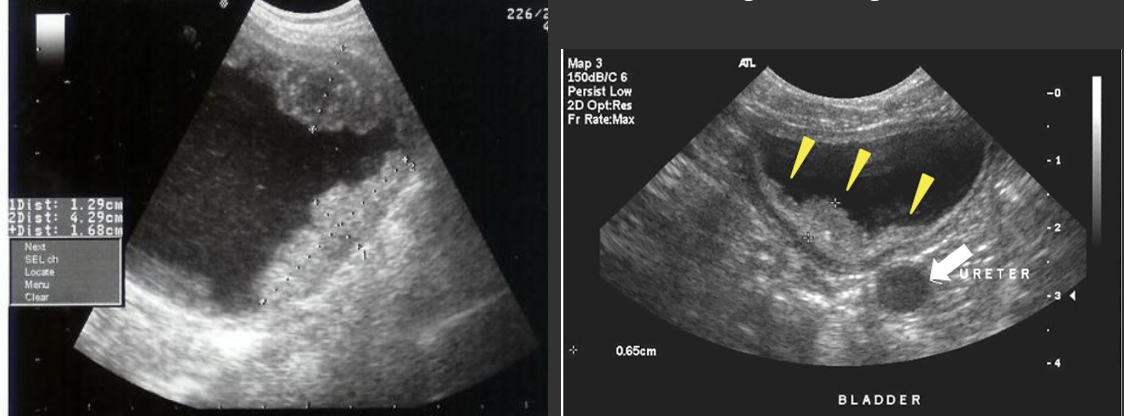

Hydronephrosis → dilation of renal collecting system from mechanical obstruction or functional dysfunction (calculi, mass, trauma, pregnancy)

clinical hx: prone to stones (stasis, pregnancy)

s/sx: if stone → renal colic, N&V, hematuria, frequency/urgency

2D US: grade 1 (mild) → pelviectasis, cortex preserved, grade 2 (mild to moderate) → expands into major calyces, cortex preserved, grade 3 (moderate) → expand all calyces, entire pelvis dilated, cortex preserved, grade 4 (severe) → cortical thinning, AKI to CKD, creatinine >1.2

color doppler: avascular

DDX: parapelvic cysts

Hydroureter → dilation of the ureter from BOO, ureter mass, gravida uterus, uterine fibroid compression

clinical hx: pregnancy, BPH (older males), nephrolithiasis prone (pregnancy, stasis)

s/sx: renal colic, symptoms mimic UTI (frequency, urgency)

2D US: dilated ureter at UVJ